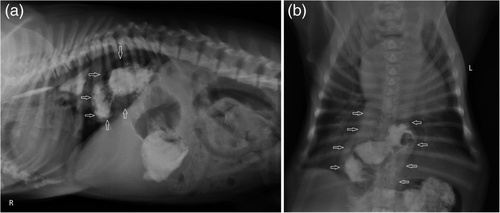

X-rays / Ultrasound